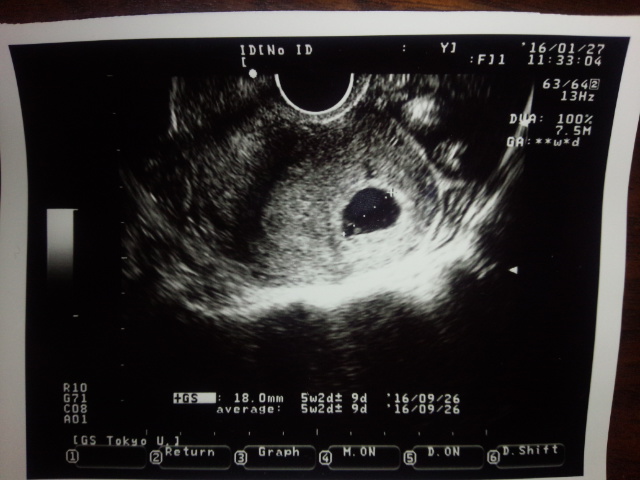

妊娠したのは素直に嬉しいとは思うし、驚いてはいるけれども

まだまだ全く実感がわいていません。

今も腹の中に一人の人間が出来上がりつつあるのが、判りません。

ツワリでだんだんと認識ができるとは言うけれども

ここまで予兆っぽいのはあるのだけれども、次の検診まで不安は長いです

実際妊娠初期の流産の確率は10%超え。

1割か。